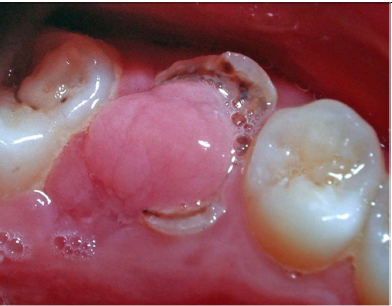

Chronic Hyperplastic Pulpitis (pulp polyp)

Chronic Hyperplastic Pulpitis

• AKA: pulp polyp

• An e_xcessive proliferation of chronically inflamed dental pulp tissue_ – granulation tissue/ fibrous tissue with inflammatory cells (like a little fibroma that

occurs from pulp tissue) ( benign soft tissue leasion)

• Location:

• Teeth with large, open carious lesions

• Primary or permanent molars

• Age: Children & young adults

• Clinical Appearance: A red or pink nodule of soft tissue protruding from the

pulp chamber and fills the entire cavity of the tooth

• Treatment: RCT or extraction of tooth